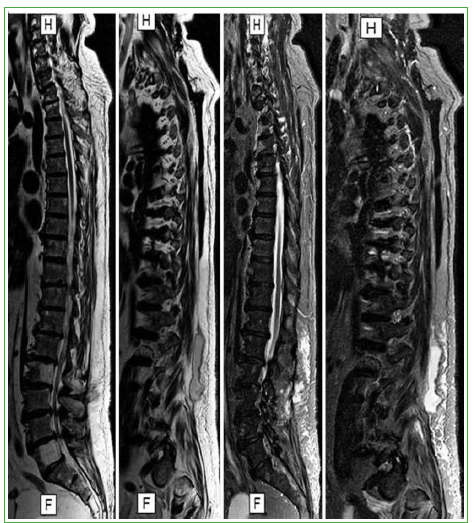

Figura 2.

Resonancia magnética de toda la columna T1, T2 y STIR, corte sagital. Se visualiza una colección hiperintensa en íntima relación con la masa muscular paraespinal derecha. Hallazgo: hiperintensidad de cuerpos de L5 y L2.